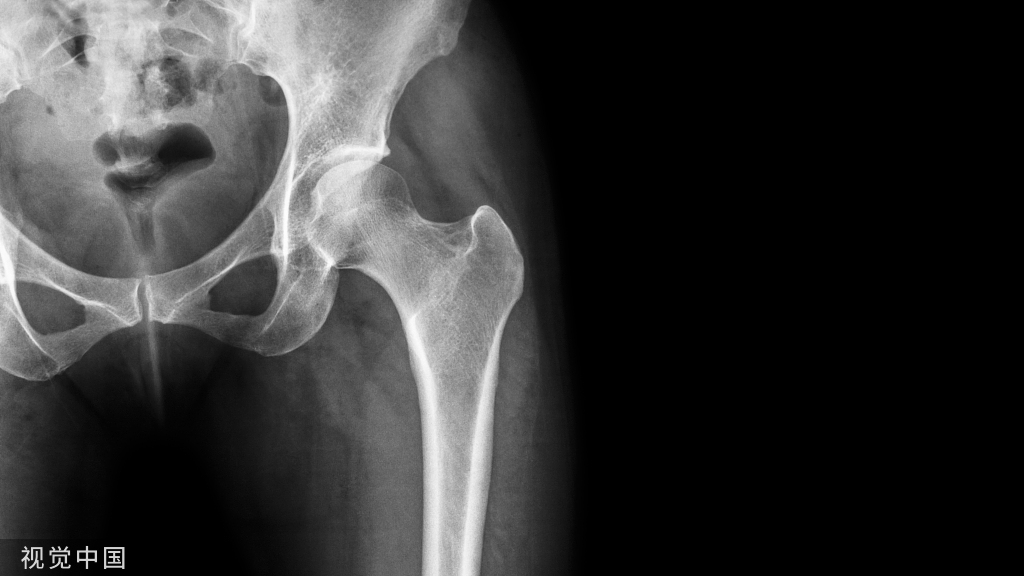

骨不连是四肢骨折术后常见并发症,治疗棘手,发病率高达 5%~10%,目前仍是全世界骨科医师临床工作中所面临的难点与挑战。

(1)骨折端有异常活动:骨折在6个月以上,作骨折端活动检查时,若有异常活动,即可诊断为骨不连。

(2)疼痛:骨端在移动时或试做负重时,产生疼痛。

(3)畸形与肌萎缩:未连接的骨折,可有成角、缩短与旋转畸形。由于长期不能使用肢体,关节挛缩畸形与肌萎缩都可出现。

(4)负重功能丧失:骨干骨折后的骨不连负重功能丧失,但某些股骨颈骨折有跛行。